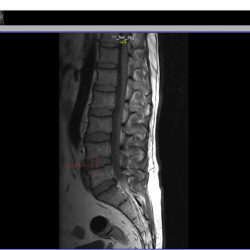

Здравствуйте. Постоянная боль в пояснице справа. Есть протрузия нижнего диска,  врач говорит, что она не должна болеть т.к. маленькая. Листая снимки заметил на соседнем диске какяю-то вертикальная полоса и темное пятно при пролистывании. Это норма или что-то ещё?